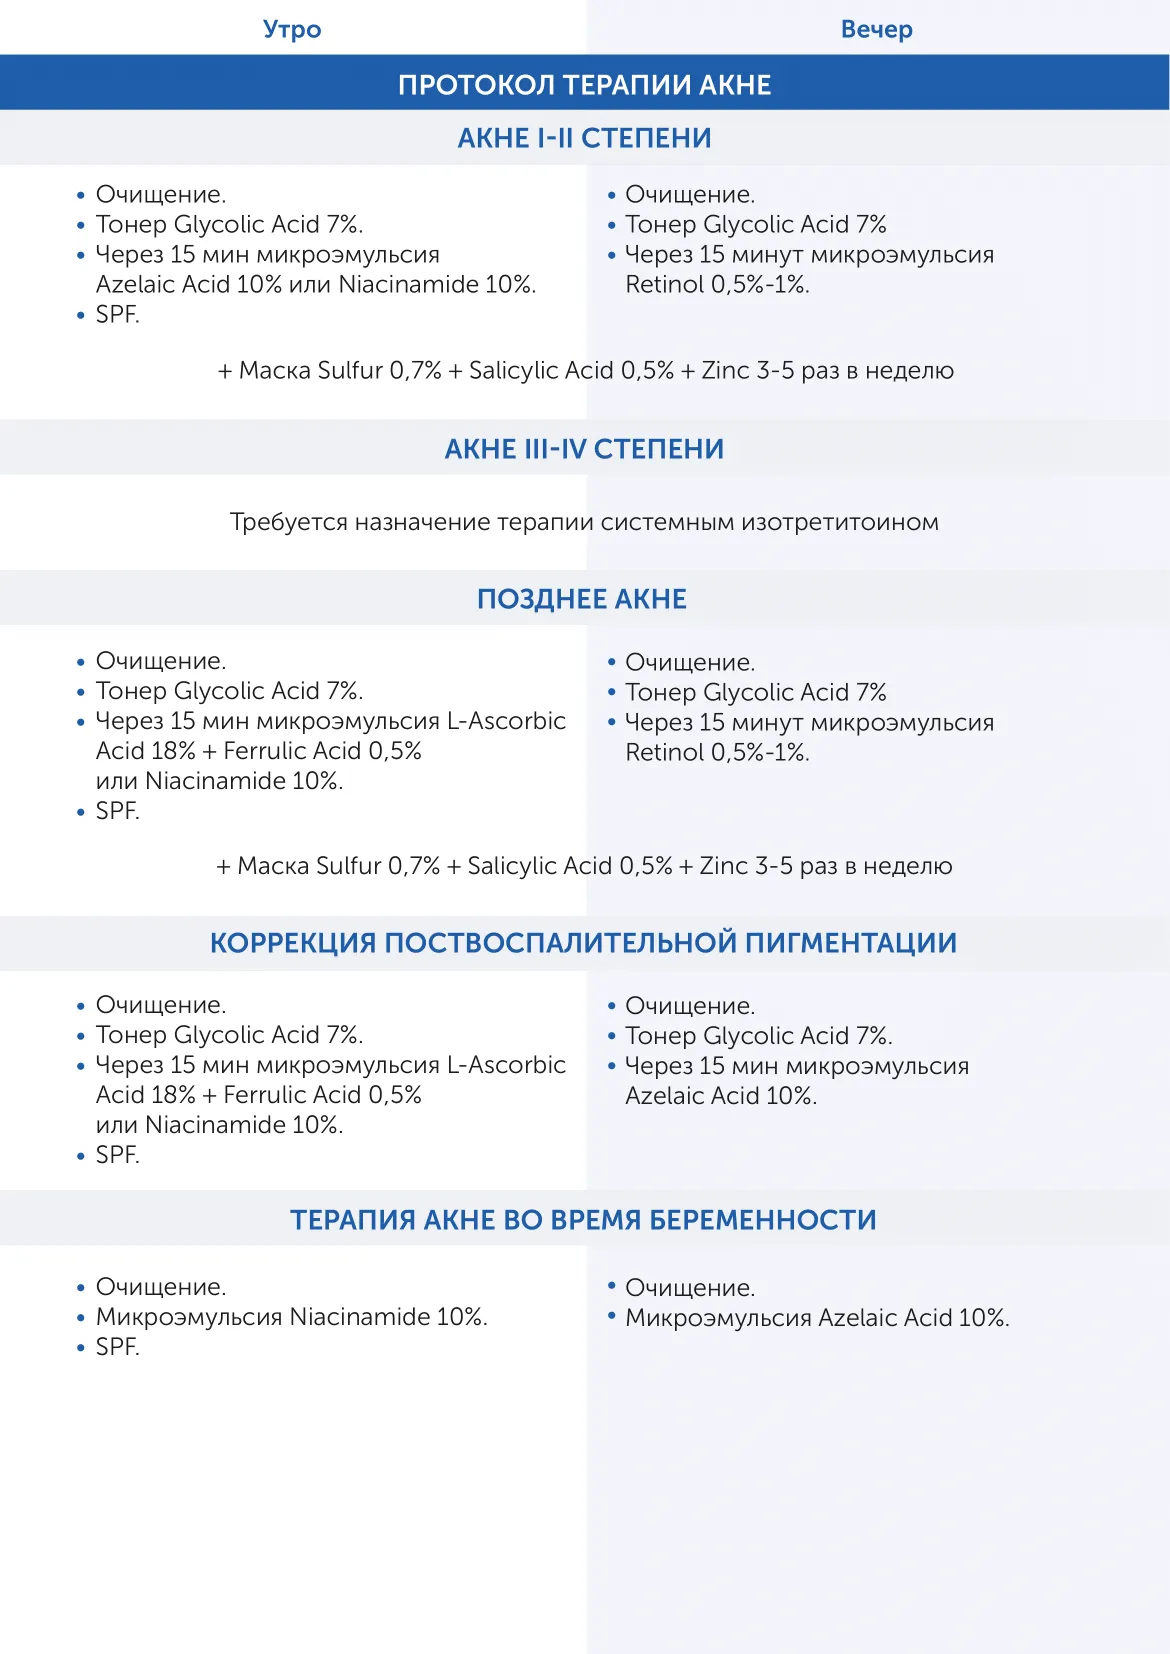

АУРИН - агентство правильных брендов, объединяющее специалистов и производителей индустрии красоты

Микроэмульсия на основе транс-ретиноевой кислоты Retinol 0,25% Skintellectual Solutions

Ретинол 0.25% (технология Hyalosphere)

AQUA

SODIUM HYALURONATE

PHENETHYL ALCOHOL

CAPRYLYL GLYCOL

AMMONIUM ACRYLOYLDIMETHYLTAURATE/VP COPOLYMER

PARFUM

RETINOL

CITRIC ACID

BHT

BHA

Возрастные изменения, нарушение пигментации кожи

Описание

Микроэмульсии Skintellectual Retinol, в основе которых лежит транс-ретиноевая кислота, по-настоящему преображают кожу. Их эффективность в борьбе с морщинами, угревой болезнью и пигментацией – медицинский факт. Максимально результативное действие микроэмульсий основано на запатентованном способе доставки Hyalosphere™, что дает им более глубокое пронивкновение в кожу и более длительное сохранение высокой концентрации активного ингредиента (до 6 часов). Компонент

проникает в глубокие слои кожи, деликатно устраняя возрастные

проблемы разглаживает морщины, осветляет пигментные пятна,

выравнивает тон и текстуру кожи,а разное процентное содержание ретинола (от 0,25% до 1%) в микроэмульсии позволяет минимизировать риск нежелательных реакций. Требуется консультация дерматокосметолога.